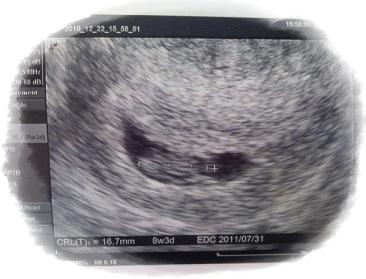

エコー写真は心拍が確認できてから2回目の写真です(8w1dのとき)。

胎児が約17mmになっていました。